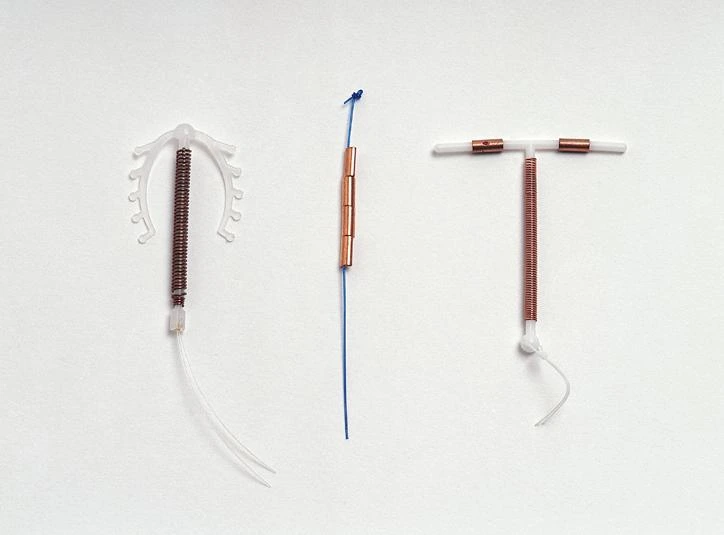

- Regular Contraceptive Use: Emergency contraception is not meant to be a primary contraceptive method. In cases of regular unprotected intercourse or contraceptive failure, other contraceptive options like contraceptive pills, intrauterine devices, or condoms should be considered.

EC or “morning after” pills are not the only option available. The most effective method of emergency contraception available is the copper IUD. When correctly inserted by a clinician within 5 days of unprotected sex, the IUD has a success rate of over 99%. If used as a primary or secondary method of contraception, the copper IUD also provides a long-term option, but it does require a visit.

Like most other forms of contraception, emergency contraception pills are not designed to be used as the main means of birth control. For long-term prevention of pregnancy, more effective methods, such as regular birth control pills, an intrauterine device (IUD), or even condoms, should be used.